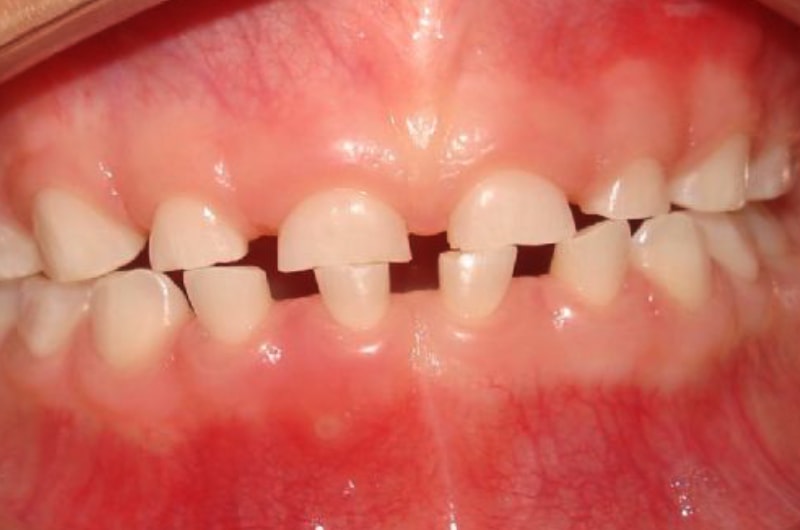

BRUXISMO NA INFÂNCIA

O bruxismo é o ato de apertar ou ranger os dentes. Pode acontecer de dia ou durante o sono e ser de forma consciente ou inconsciente. O bruxismo infantil não tem uma causa única. Por ser de etiologia complexa e apresentar consequências em diversas estruturas, o bruxismo deve ser tratado de maneira multidisciplinar, envolvendo tratamento em parceria de dentistas, fisioterapeutas, médicos, psicólogos e fonoaudiólogos.